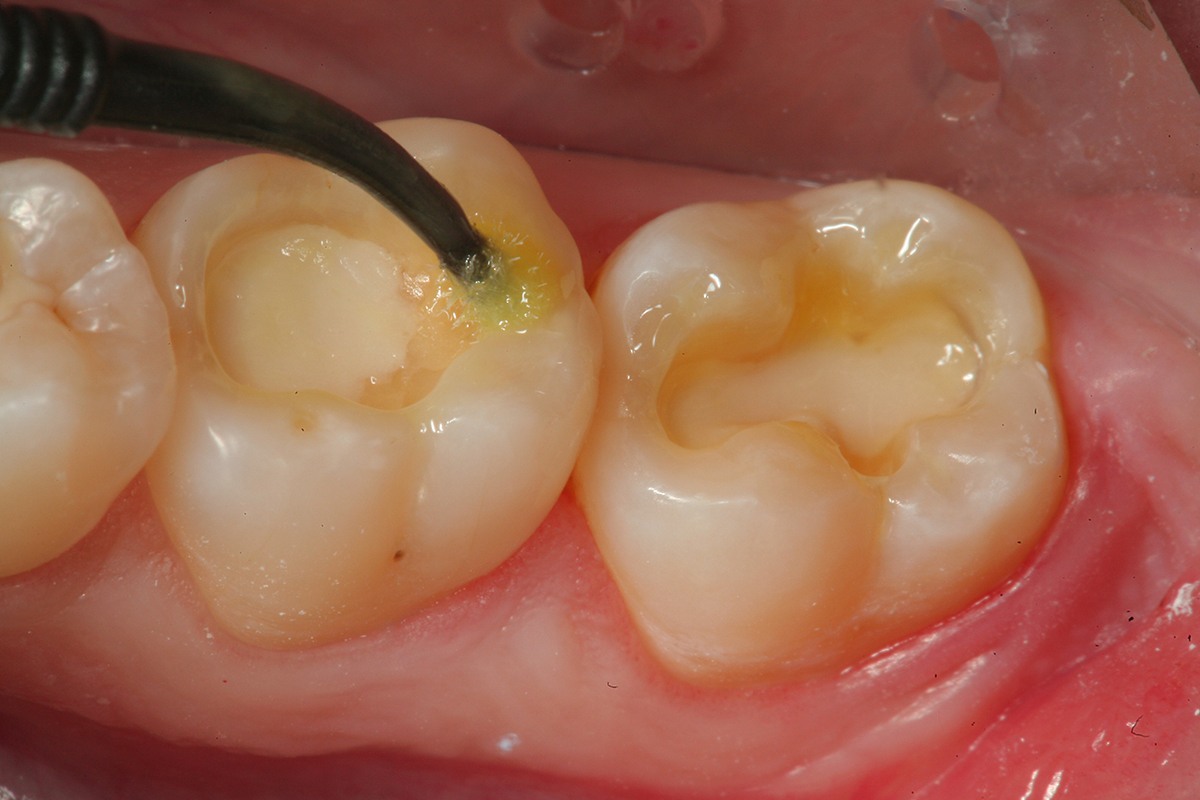

Fig 10. After removal of the existing restorations and associated recurrent decay, both cavities are very deep and there is a pinpoint pulpal exposure on tooth No. 19.

Figure 10